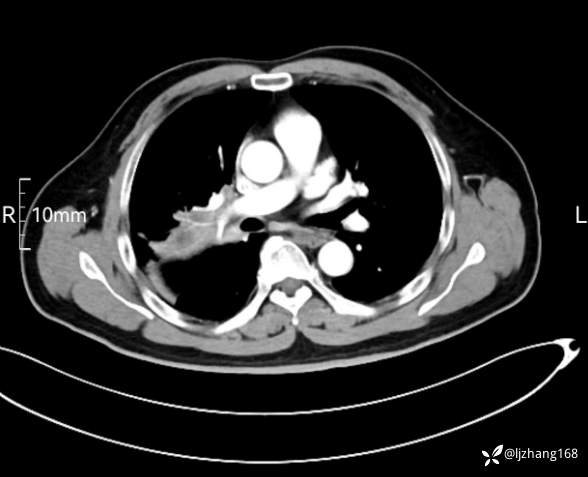

中年男患,右肺团片影,炎症0R肿瘤?

辅助检查:糖化血红蛋白12.3%。肺炎支原体IgG、IgM、呼吸道合胞病毒均未见明显异常。胸部CT:右肺上叶阻塞性肺炎。